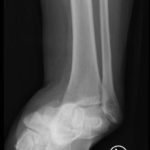

The X-rays were significant for a subtalar dislocation. The calcaneus (red) is laterally displaced with respect to the talar head (orange), and the white lines indicate the normal articular surface. Additionally, there was a talonavicular dislocation, as seen in the fourth image: the talus (green) and navicular bone (purple) overlapping suggests a dislocation. In a normally aligned foot, the boundaries of the two bones create a point of articulation.

Proper diagnosis of talonavicular dislocations require obtaining anteroposterior (AP), lateral, and mortise views of the ankle and foot.3 The utility of computed tomography (CT) in diagnosis has also been discussed. One study reported that 44% of patients who received CT for subtalar dislocation had a treatment plan differing from that based on plain film findings.4 Specifically, CT identified fractures that were not visible on plain films as well as intraarticular debris requiring evacuation in an effort to promote proper healing and function.